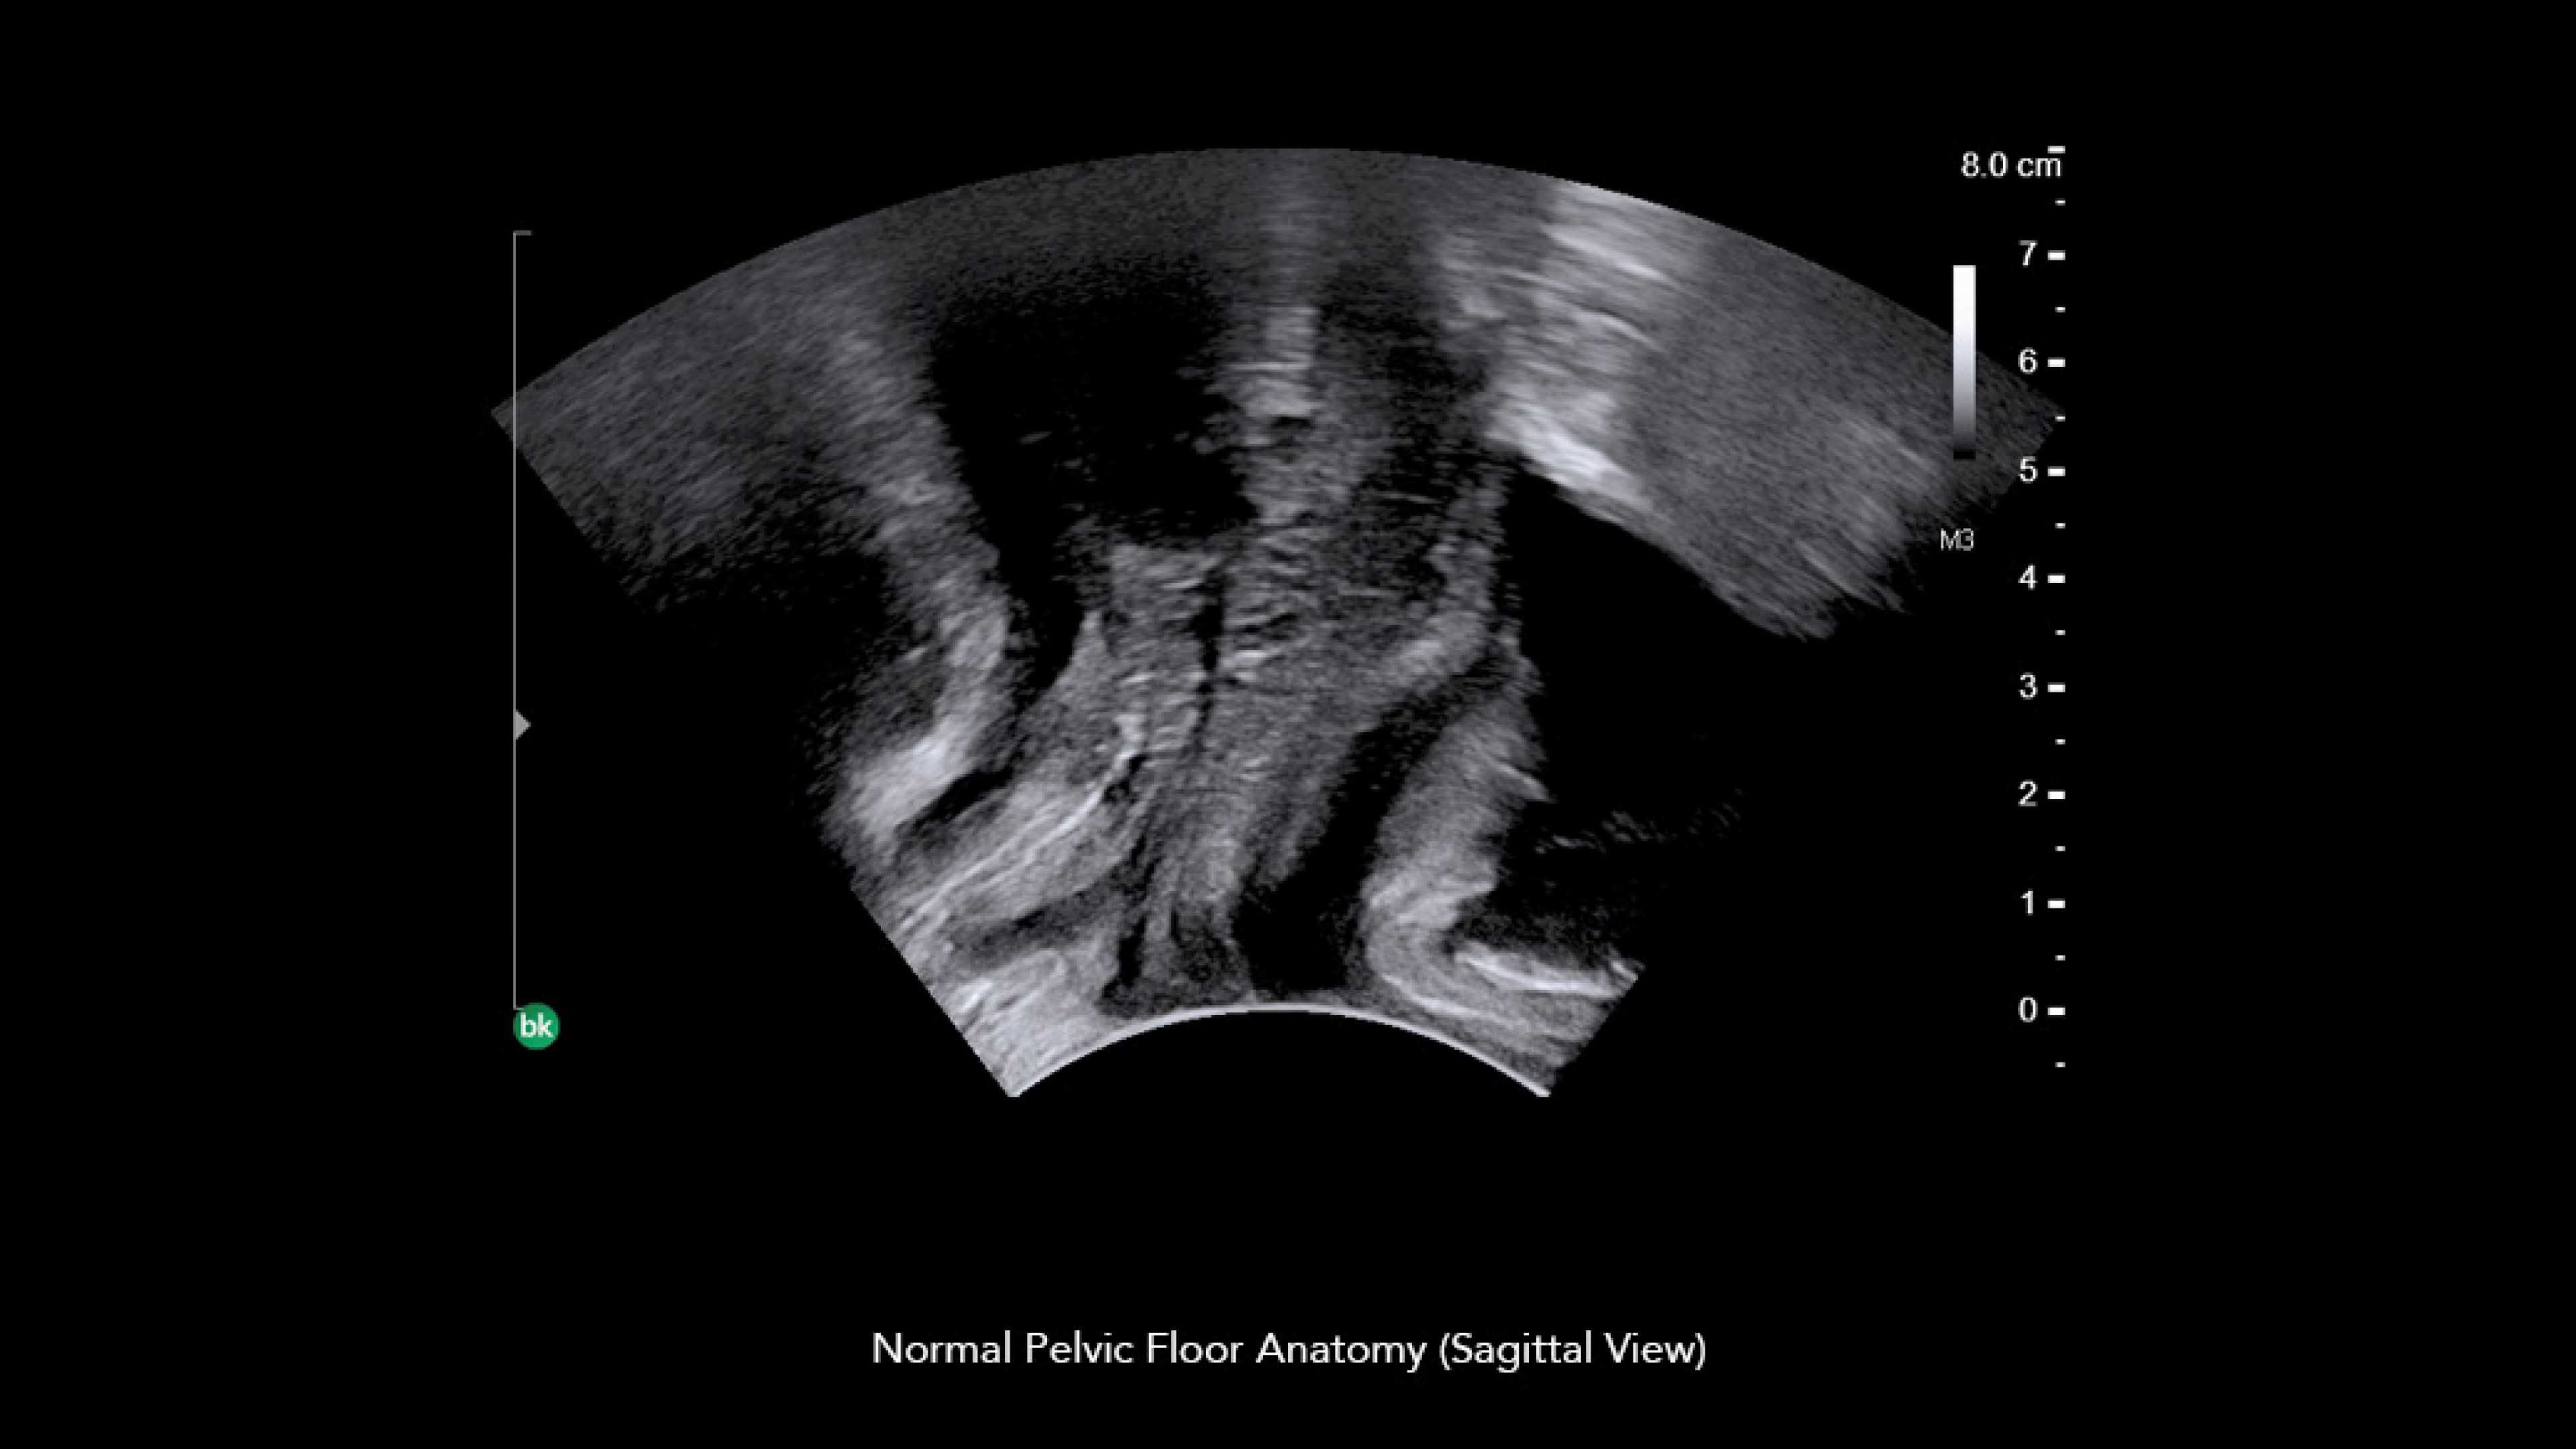

Surgical Visualization and Guidance has you covered with the latest innovations in ultrasound-guided solutions for urology. Using patented ultrasound technology and sophisticated software algorithms, our real-time imaging platform enables urologists to guide urology procedures with confidence. Our complete portfolio supports urologists ranging from the clinic to the OR.